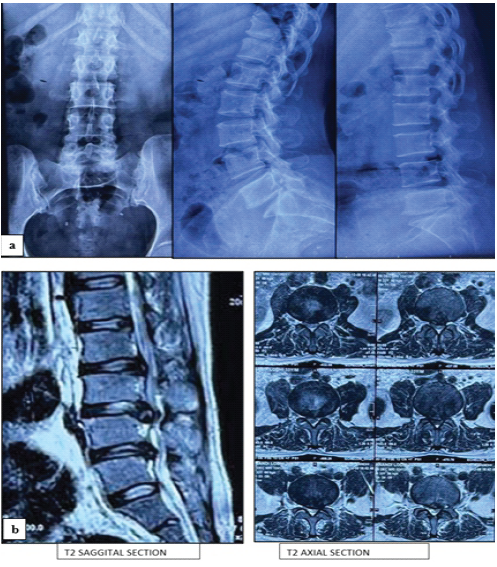

The required sample size was computed using the standard formula based on an estimated prevalence of lumbar disc prolapse of 1.7% (P = 0.017), with a confidence level of 95% (Z = 3.84) and an allowable margin of error of 13% (d = 0.13). The minimum calculated sample size was 32 subjects [10]. Furthermore, all consecutive patients meeting the inclusion criteria and operated during the study period were enrolled to enhance the power of the study. Patients undergoing UBES for symptomatic lumbar spine disorders at a tertiary care center, Hamidia Hospital, associated with Gandhi Medical College, Bhopal, Madhya Pradesh, were considered for inclusion in the study. Inclusion criteria comprised adult patients (age ≥18 years) diagnosed clinically and radiologically by X-ray and magnetic resonance imaging (Fig. 1a and b) with lumbar disc herniation or disc prolapse refractory to conservative management for at least 3 months. Patients with previous lumbar spine surgery, significant comorbidities precluding surgery, or incomplete follow-up data were excluded.

Figure 1: (a) Pre-operative X-ray anteroposterior and dynamic view, (b) Pre-operative magnetic resonance imaging.